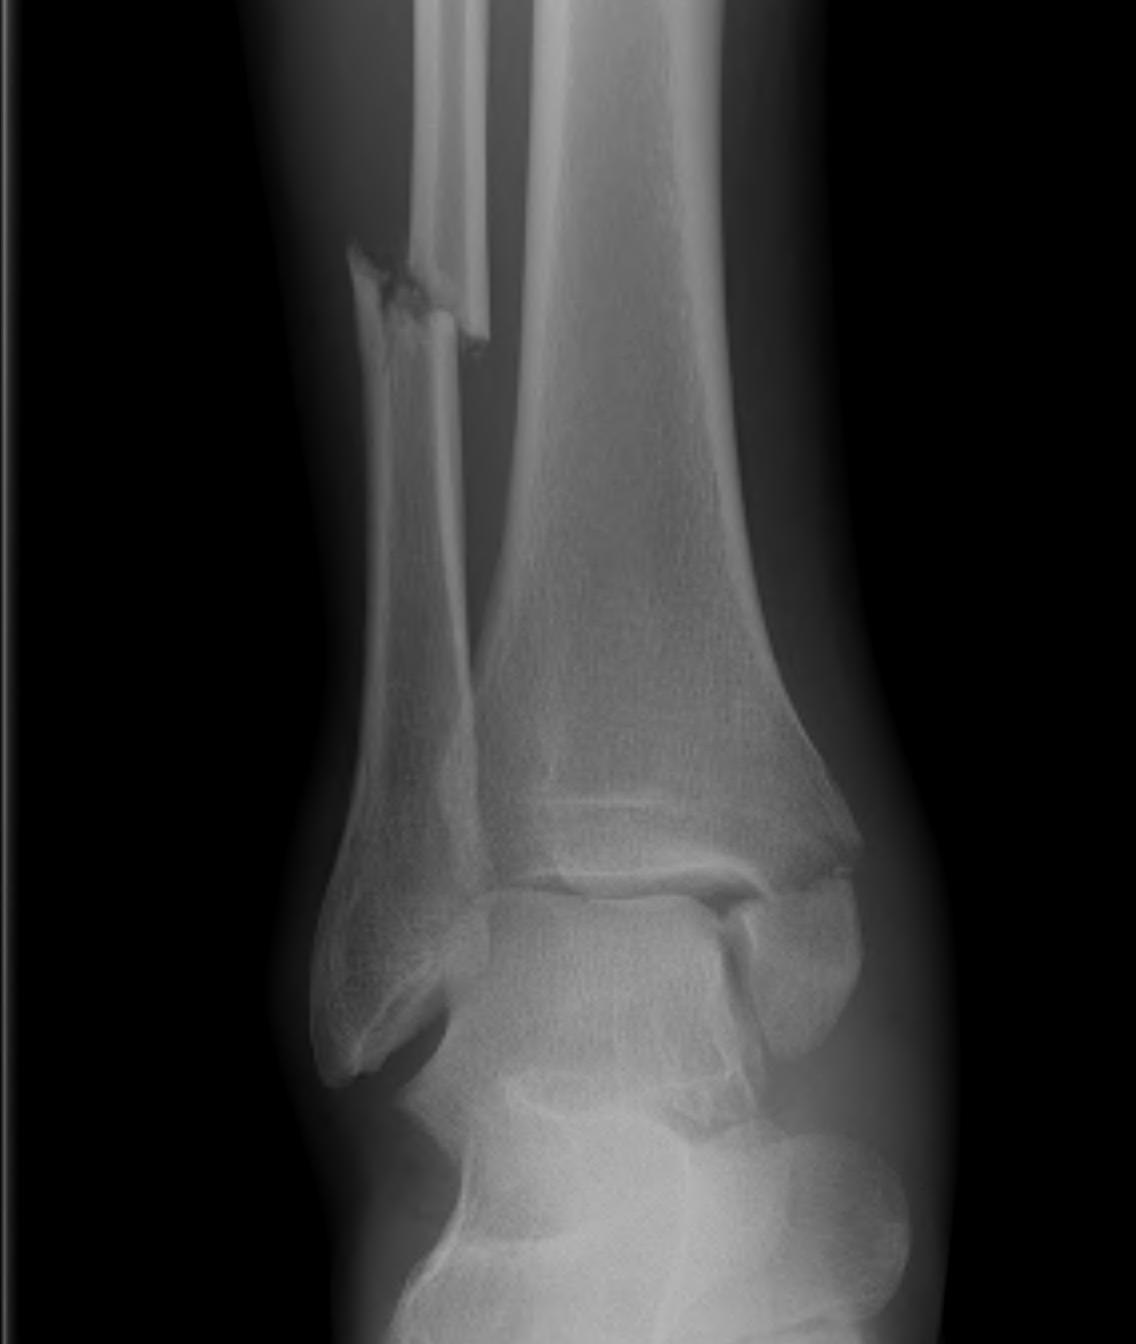

Ankle Fracture Classification

Weber Classification of fibular fractures

| Weber A | Weber B | Weber C |

|---|---|---|

| Fracture distal to syndesmosis | Fracture at level of syndesmosis | Fracture above level syndesmosis |

|

Stable - avulsion fracture |

Stability depends on deltoid ligament

Stable - no increased medial clear space / deltoid ligament intact Unstable - Increased medial clear space / deltoid ligament rupture |

Unstable

Syndesmosis disrupted |